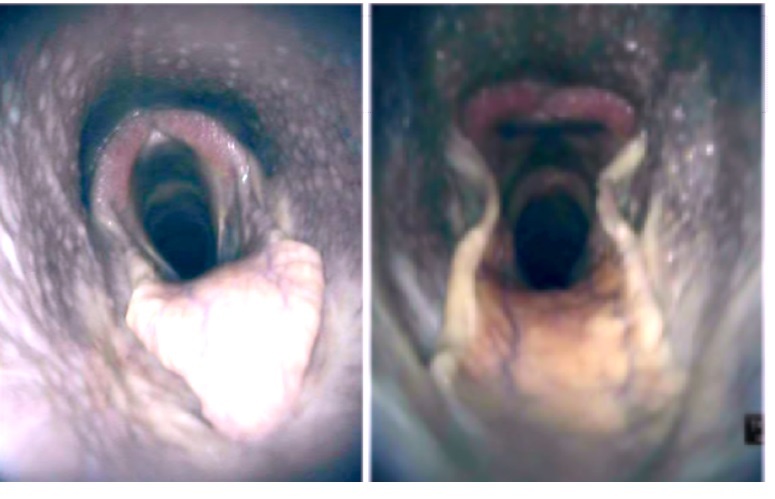

FIGURE 15 Caudoventral window – transverse plane: A, The left Plica vocalis at 6-12 months postsurgery. Plica vocalis base (white arrow) is

hyperechoic compared to the right Plica vocalis. This is consistent with thickening of the tissue in this area, attributed to a granuloma. There is a

luminal ringdown artifact created by this mass. Right to the left of image and the skin/ventral at the top. B, The corresponding right Plica vocalis at

6-12 months postsurgery on endoscopy. The Plica vocalis granuloma can be clearly seen (white arrow). Right to the left of the image [Color figure

can be viewed at wileyonlinelibrary.com]